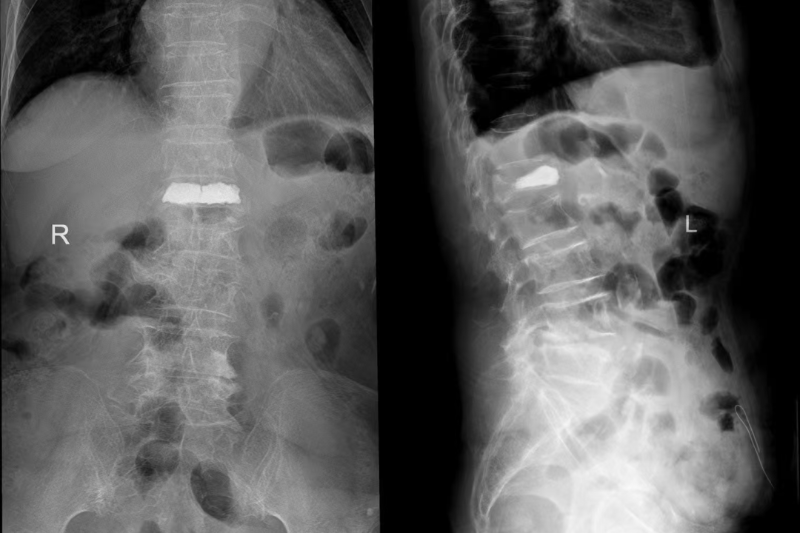

術前X線

術后X線